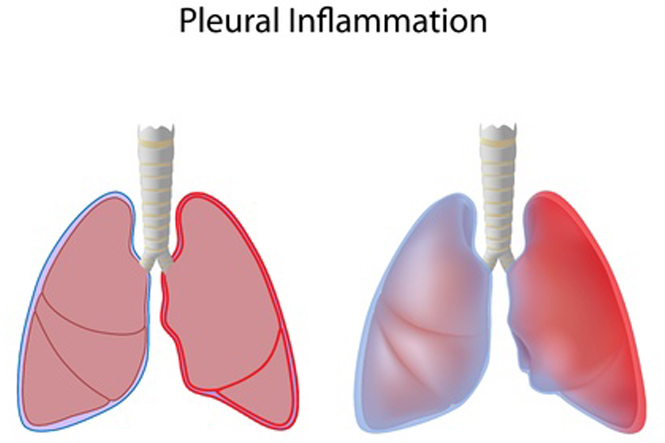

Respiratory diseases

Respiratory diseases are conditions that affect any of the processes involved with breathing. If you or someone you know are one of the 1 in 6 New Zealanders that lives with a respiratory condition, here you can find some useful information on how to manage the condition well.